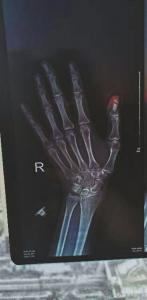

随后,李女士和男友给住在附近的朋友打了电话,让朋友开车送他们去医院。到了医院,经检查后发现,李女士的大拇指开放性骨折,必须做手术,“本来以为只是个平常的外伤,结果一听手术才知道糟糕了。为了节约手术费,我连续换了三家医院,才找到一家稍微便宜点的。”

李女士说,她在汽车驶离的一瞬间,感到撕心裂肺的疼痛,“当时我右手的大拇指已经被车门夹住了,他的车速又比较快,导致我大拇指的指甲盖硬生生被扯掉了大半个。”李女士说,当时她的手指就血肉模糊,她疼得蹲在了地上,而司机也不知道是没发现还是故意不管,直接就开车离开了。